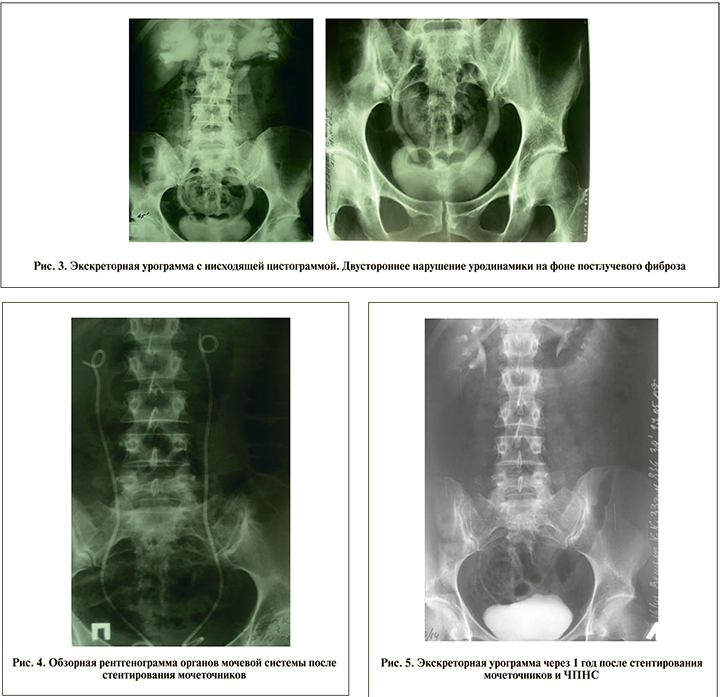

П а ц и е н т к а В. 36 лет. В 2004 г. во время беременности диагностирован РШМ III стадии, выполнено кесарево сечение, затем лечение РШМ: сочетанная лучевая терапия (дистанционная лучевая терапия – 34 Гр, внутриполостная терапия – 153 Гр). В марте 2006 г. диагностированы поздний лучевой эрозивный ректит, постгеморрагическая анемия, проводилась консервативная терапия. В июле 2006 г. впервые возникла макрогематурия, диагностирован лучевой цистит, внутритазовый лучевой фиброз со сдавлением обоих мочеточников (рис. 3); выполнено стентирование обоих мочеточников (рис. 4), проводилась консервативная гемостатическая терапия с временным эффектом.

В ноябре 2006 г. поступила в клинику с жалобами на слабость, тошноту, рвоту, боли внизу живота, наличие примеси крови в моче со сгустками, повышение температуры тела до 38°С. На фоне тампонады мочевого пузыря – атака пиелонефрита, купированная после ликвидации тампонады, двусторонней чрескожной пункционной нефростомии (ЧПНС), удаления стентов, гемостатической, антибактериальной терапии. Проведен курс инстилляций диоксидином, димексидом.

Гематурия повторялась неоднократно, проводилась гемостатическая и местная терапия амбулаторно и в стационарных условиях. Последняя госпитализация в 2011 г. по поводу очередного эпизода макрогематурии. При обследовании исключен рецидив основного заболевания, нарушения уродинамики отсутствовали (рис. 5).